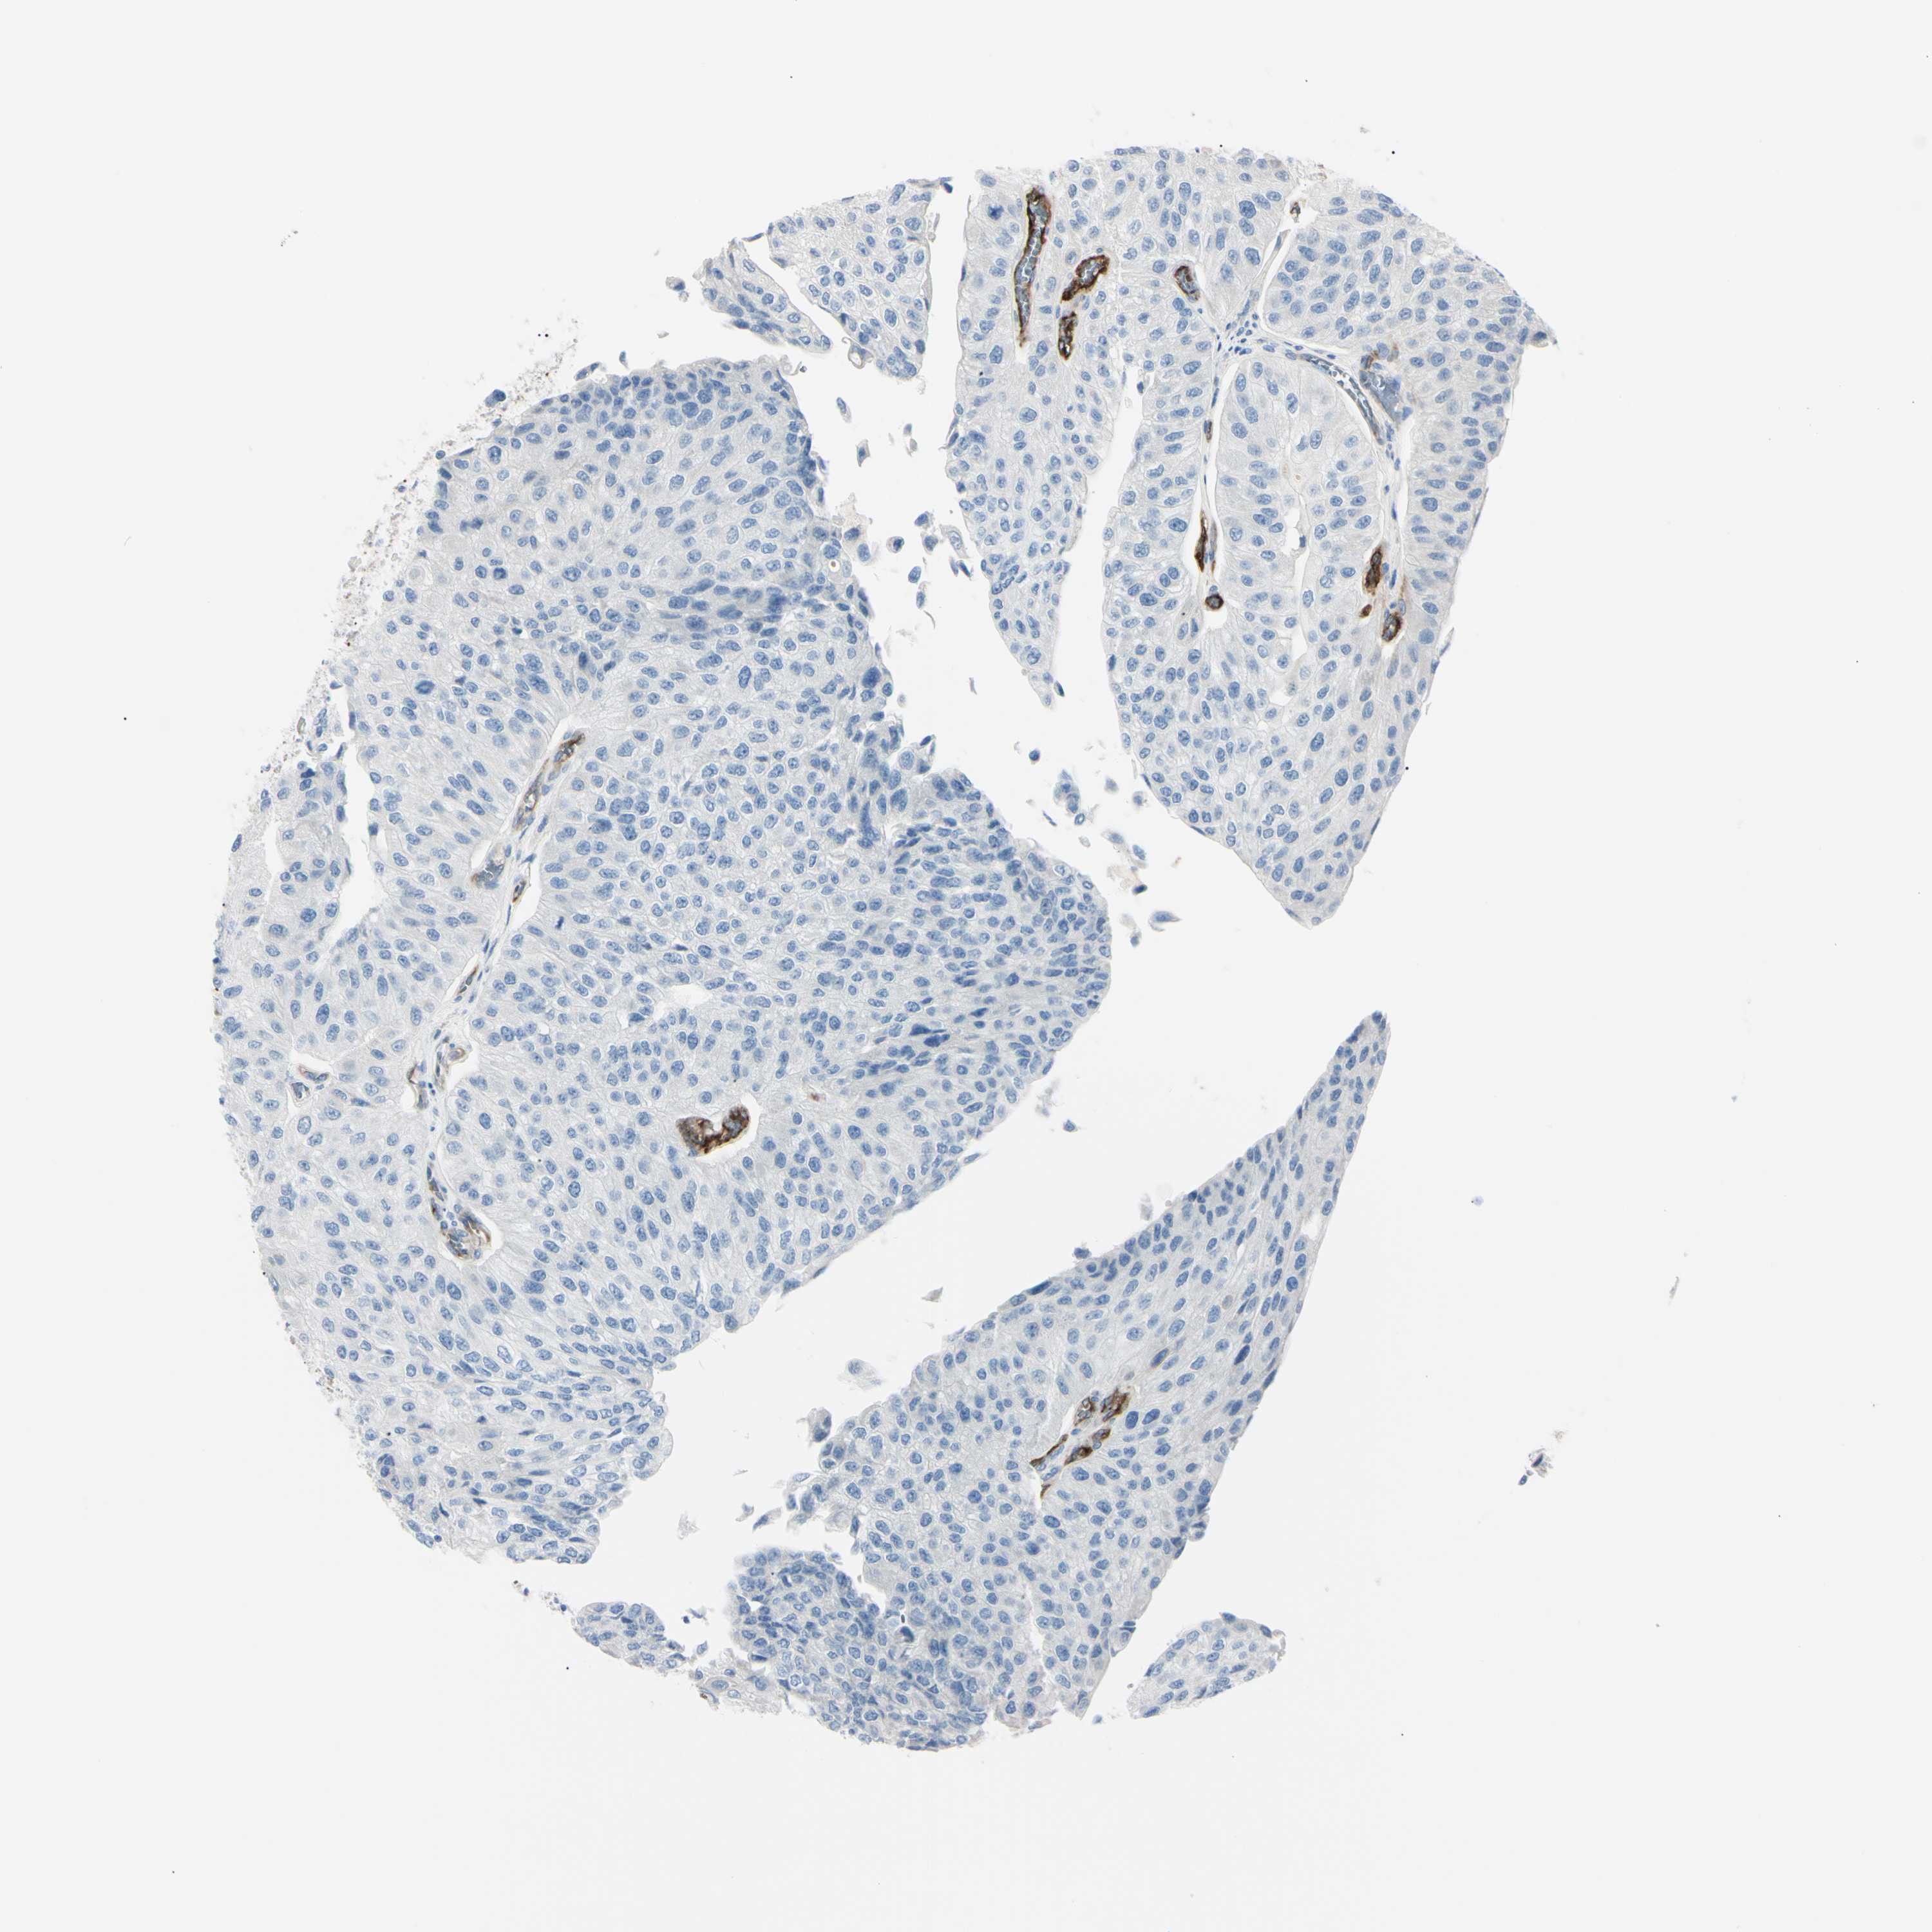

UROTHELIAL CANCER - Protein expressioni

A mouse-over function shows sample information and annotation data. Click on an image to view it in a full screen mode. Samples can be filtered based on level of antibody staining by selecting one or several of the following categories: high, medium, low and not detected. The assay and annotation is described here.

Note that samples used for immunohistochemistry by the Human Protein Atlas do not correspond to samples in the TCGA dataset.

Antibody stainingi

Antibody staining in the annotated cell types in the current human tissue is reported as not detected, low, medium, or high, based on conventional immunohistochemistry profiling in selected tissues. This score is based on the combination of the staining intensity and fraction of stained cells.

Each image is clickable and will lead to virtual microscopy that enables deeper exploration of all samples and also displays staining intensity scores, fraction scores and subcellular localization as well as patient and tissue information for each sample.

Antibody HPA010593

Antibody CAB001451

Urothelial carcinoma, Low grade

Urothelial carcinoma, High grade

Adenocarcinoma, NOS